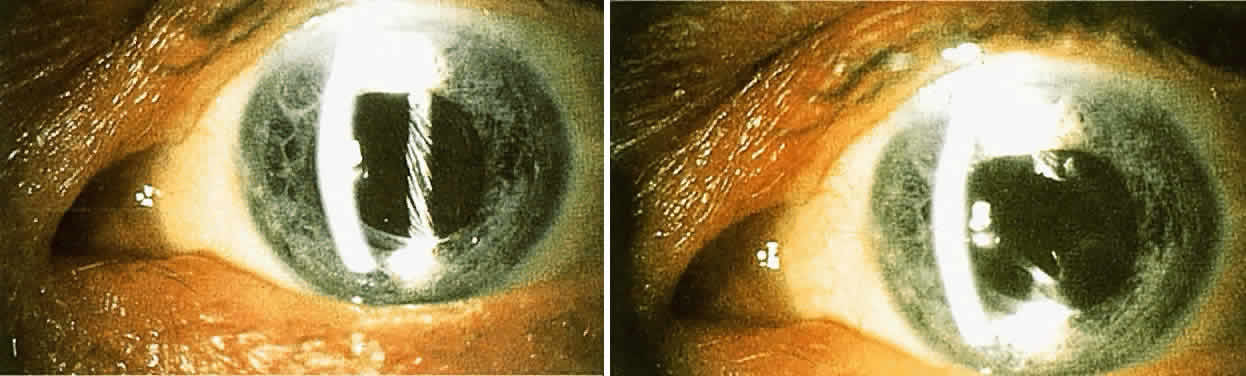

Surgical Methods When these methods fail to help a patient who has glare disability, surgical

removal of the scattering lesion should be considered. Significant

corneal edema or permanent corneal scars can be treated by a corneal

transplant. A significant cataract should be extracted. Finally, an

opaque lens capsule after cataract surgery, which produces glare symptoms

or reduced contrast sensitivity, requires a capsulotomy. Because the

glare disability is proportional to the ratio of the area of capsule

opening over the area of capsule opacity, the size of the capsulotomy

must be considered. The size of the optimal capsulotomy equals the size

of the pupil (Fig. 11).18  Fig. 11. Top. Opaque lens capsule (note diagonal lines in capsule). Bottom. Same capsule with laser-made opening. Fig. 11. Top. Opaque lens capsule (note diagonal lines in capsule). Bottom. Same capsule with laser-made opening.